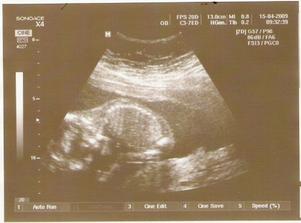

15.4. - kontrola proběhla v pořádku, mimi na nás strkalo záda, nechtělo se ukázat, ale jelikož jsem pana doktora prosila o fotečku, tak se snažil ho najít z boku - musel z boku mého břicha hledat až ho našel v přijatelné poloze... - vidíte na uzv - cucá si palec u nohy. Jen mě někdo uklidněte... že to že tam jsou vidět jen prtavé ruce, že je to tím, že je nechytil uzv? že je mimi v pořádku???